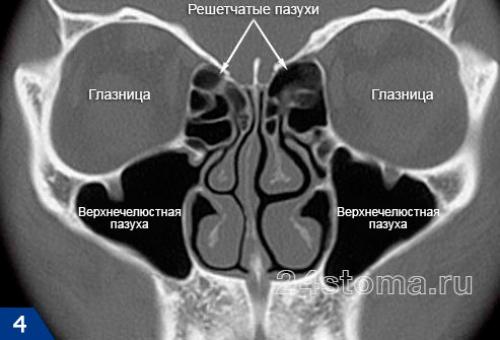

Синусит (от лат. sinusitis) – это воспаление слизистой оболочки, которая выстилает изнутри придаточные пазухи носа. Воспаление может локализоваться только в одной из пазух, либо сразу в нескольких. Чаще всего воспалению подвержены верхнечелюстные синусы (гайморовы пазухи), которые расположены в проекции верхушек корней 5-6-7 зубов с каждой стороны верхней челюсти. Такое заболевание принято называть терминами – верхнечелюстной синусит или гайморит (рис.2).

Синусит (помимо верхнечелюстных пазух) может также локализоваться в лобных пазухах, клиновидных пазухах, а также в ячейках решетчатой кости. Для его обозначения в этих случаях используются термины – фронтит, сфеноидит и этмоидит, соответственно. Однако, чаще всего пациентам приходится сталкиваться именно с верхнечелюстным синуситом, что связано прежде всего с некоторыми анатомическими особенностями верхнечелюстных пазух.

Таких пазух две (по одной с каждой стороны верхней челюсти). Средний размер верхнечелюстных пазух у взрослого: от 2,5 до 3,5 см – в ширину, от 3,6 до 4,5 см – в высоту, от 3,8 до 4,5 см – в глубину. Заполнены пазухи воздухом, а внутренняя их поверхность выстлана слизистой оболочкой. На рис.3 вы можете увидеть, что верхняя костная стенка пазухи является одновременно нижней стенкой глазницы, а дно каждой пазухи – отделено от верхушек корней 5-6-7 зубов лишь тонким слоем костной ткани (в среднем от 1 до 3 мм).

4 основных вида околоносовых, или придаточных, пазух:

- лобные, или фронтальные, — расположены над глазами, слева и справа от переносицы;

- пазухи решётчатой кости — находятся по бокам от переносицы и состоят из ячеек;

- клиновидная, или сфеноидальная, — самая дальняя пазуха, находится глубоко за пазухами решётчатой кости;

- верхнечелюстные, или гайморовы, — самые большие пазухи носа, расположены под глазами.